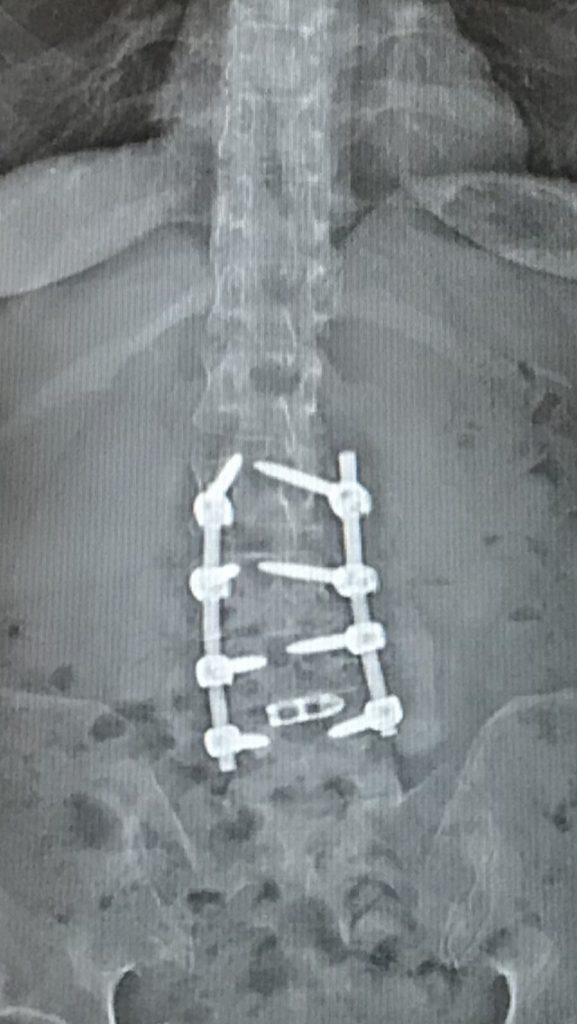

After seeing my entire spine, Dr. Kim talked to me about my lumbar spine. I knew that I had degenerative scoliosis, spondylolisthesis, and stenosis. I could not walk more than 3 city blocks without having to sit down. I did everything with pain and was putting off surgery. Epidurals, PT and acupuncture stopped working for me. Dr. Kim recommended an L2-L5 spinal fusion and I had this done 4 months after my cervical spine surgery.